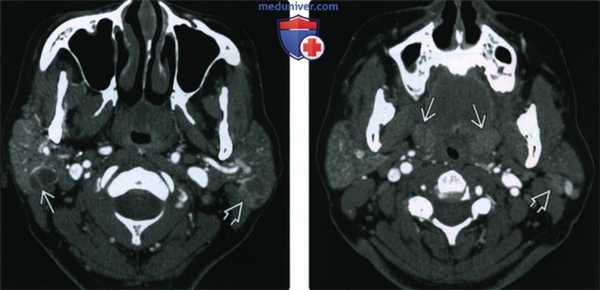

(Слева) КТ с КУ, аксиальная проекция. В обеих околоушных железах визуализируются солидные образования с четкими контурами. И хотя метастазы и лимфома могут выглядеть точно так же, гипертрофия небных миндалин позволяет заподозрить лимфоэпителиальное поражение или хроническую лимфаденопатию околоушных лимфоузлов при ВИЧ.

(Справа) КТ с КУ, единичная киста в левой околоушной железе, разделенная внутренней перегородкой. И хотя при доброкачественном лимфоэпителиальном поражении обычно обнаруживается сразу несколько образований, иногда они могут быть и единичными. В такой ситуации может быть выставлен неверный диагноз - киста первой жаберной щели.

(Слева) КТ с КУ, аксиальная проекция у пациента с объемным образованием шеи слева. Плотность обеих околоушных желез увеличена, в правой железе определяется многокамерная киста, в левой - смешанное кистозно-солидное образование.

(Справа) КТ с КУ, аксиальная проекция, этот же пациент. Определяется единичный увеличенный околоушной узел слева и гипертрофия небных миндалин. По результатам КТ пациенту было рекомендовано обследование на ВИЧ, результат оказался положительным.